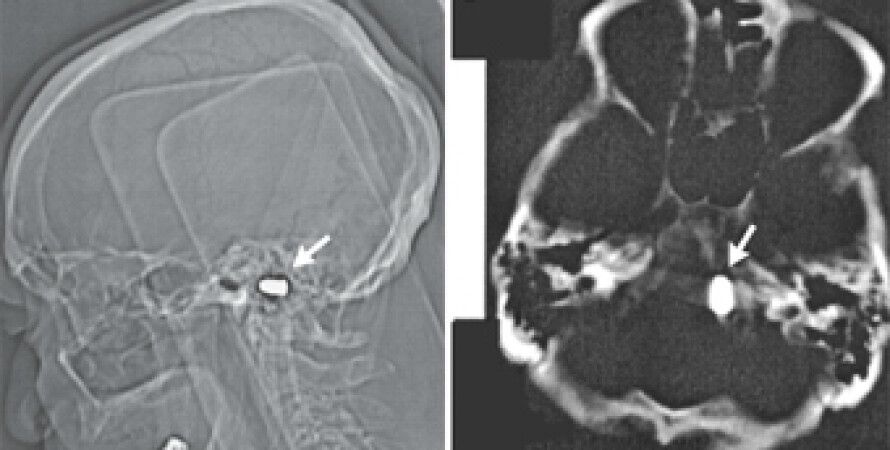

Тем не менее, сотрудники кардиоцентра доктор наук Марат Ежов, научный сотрудник отдела проблем атеросклероза Института клинической кардиологии РКНПК и ординатор этого отдела Майя Сафарова решили перестраховаться и назначили мужчине компьютерную томографию головы. Исследование показало, что у него в области большого отверстия затылочной кости находится пуля. При этом инородное тело не давило на жизненно важные органы и не вызывало опасных изменений в окружающих тканях.

Учитывая крайне низкий риск, связанный с нахождением пули в полости черепа, и пожилой возраст пациента, врачи сочли удаление инородного предмета нецелесообразным. Они лишь предупредили мужчину, что магнитно-резонансная томография головы ему противопоказана, поскольку сильное магнитное поле томографа может сместить пулю.